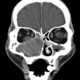

Ethmoid sinus cancer

The ethmoid sinuses or ethmoid air cells of the ethmoid bone are one of the four paired paranasal sinuses. The cells are variable in both size and number in the lateral mass of each of the ethmoid bones and cannot be palpated during an extraoral examination. [Source: Wikipedia ]